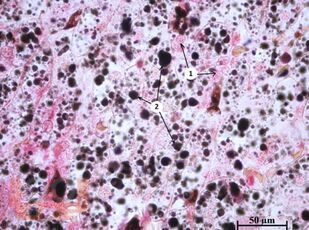

Руководство к практическим занятиям по цитологии и общей гистологии состоит из оригинальных цветных фотографий, каждая из которых сопровождается описанием и указанием учебных элементов. Описание фотографий соответствует принятой в 2009 г. Международной терминологии по гистологии и цитологии. Каждый раздел завершается перечнем вопросов, которые позволяют осуществлять самоконтроль усвоения изученного материала. Разделы руководства структурированы в соответствии с рабочими программами дисциплин «Общая морфология, цитология», утверждёнными в СибГМУ.